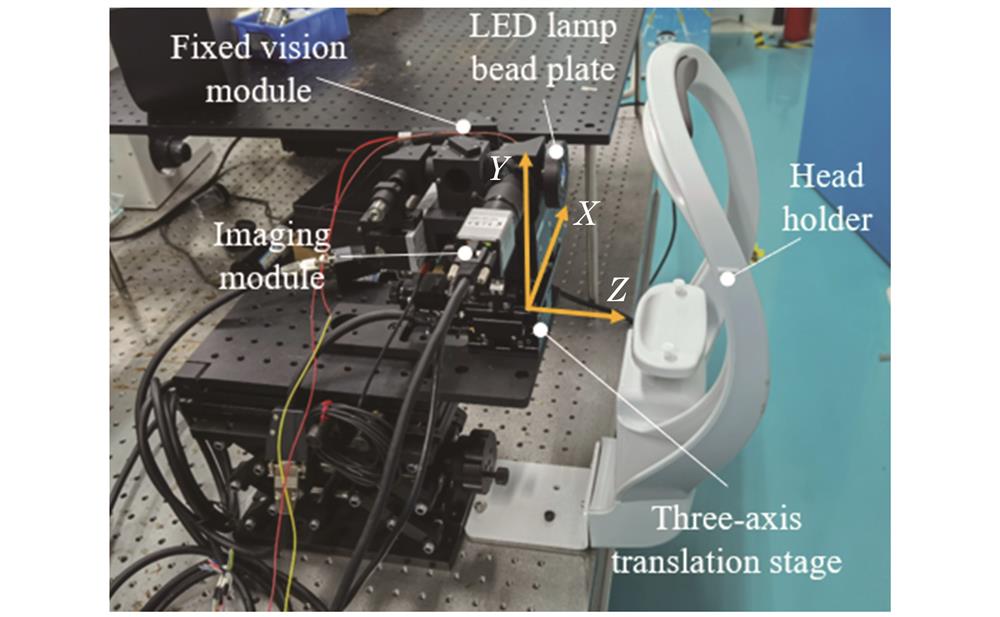

A human eye autofocus and pupil center auto-alignment system for ophthalmic measuring instruments is built. The system is mainly composed of a fixed vision module, an LED lamp bead plate, an imaging module, a three-axis electric displacement stage, and a head holder. By analyzing the characteristics of human eye images, an autofocus algorithm based on a four-neighborhood-multi-directional and two-level gradient function (FMTG algorithm) was proposed. The algorithm replaces the center pixel with the mean value of the center pixel and the four-neighborhood pixel for calculation, calculates the two-level gradient in the horizontal direction, vertical direction, and direction with an oblique of 45° at the same time, and takes the product of the two-level gradient operators as the sharpness evaluation value. A pupil center positioning algorithm (LPC algorithm) based on the intelligent region of interest (ROI) window of a convolutional neural network was proposed. The algorithm extracts the image coordinates of the pupil center and optical axis for alignment through steps including the extraction of the pupil region of interest, histogram-based binarization segmentation, and high-precision ellipse recognition and fitting. The performance of the proposed FMTG algorithm was verified by the system built in this paper and by actually shooting four groups of human eye-defocused image sequences. Six commonly used evaluation functions were selected for comparison, and their normalized sharpness evaluation curves were drawn. Three quantitative indicators, namely, single-frame processing time, sharpness ratio, and sensitivity, as well as two important properties such as unimodality and accuracy, were selected to comprehensively evaluate the performance of the functions. The performance of the proposed LPC algorithm and other algorithms for comparison was evaluated in terms of the average computation time, accuracy, and average error through the test set of real-shot human eye images. In addition, the proposed LPC algorithm was tested under complex conditions with different illumination and partial pupil occlusion to evaluate the universality of the algorithm.

2 系统组成

应用于眼科测量仪器的人眼自动对焦及瞳孔中心自动对准系统如

图 1. 人眼自动对焦及瞳孔中心自动对准装置组成结构

Fig. 1. Structure of human eye auto-focus and pupil center auto-alignment device

本文设计了两组实验分别用于验证人眼自动对焦算法和瞳孔中心定位算法的有效性及准确性,实验图像均使用本文搭建的系统进行采集。